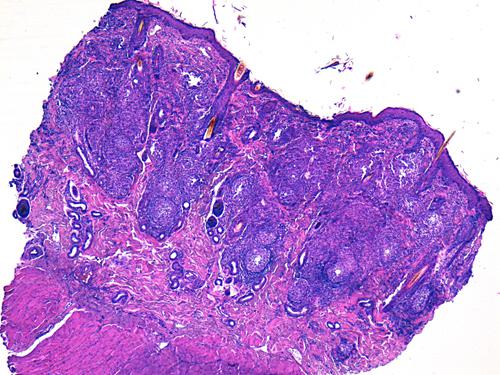

L’examen histopathologique de biopsies cutanées montre la présence d’un infiltrat dermique granulomateux de topographie périannexielle à diffuse d’intensité marquée, sans mise en évidence d’élément figuré après coloration HES, PAS et Fite-Faraco (photos 3 et 4).

cas-de-dermatite-granulomateuse-sterile-chez-chat4

Photo 4 : infiltrat composé de macrophages, polynucléaires neutrophiles,

de lymphocytes centrés autour d’un reliquat de tige pilaire,

libre dans le derme (HES, x400)